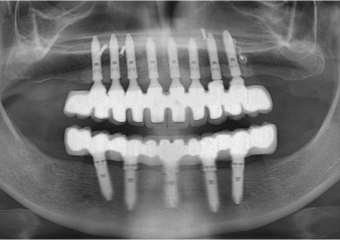

Raio X  final das próteses fixas em porcelana - Clínica Cliniface

Raio X final das próteses fixas em porcelana